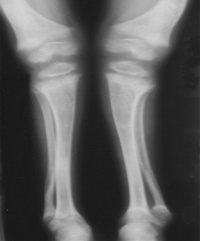

肾性佝偻病x线表现

③四肢:“手镯”及“脚镯”;开始行走后,(“O”型)或(“X”型)腿,长骨可发生青枝骨折

脊柱脊柱后凸或侧弯畸形骨盆畸形。

①X线:钙化带模糊,干骺端增宽,边缘呈毛刷状或杯口状改变。